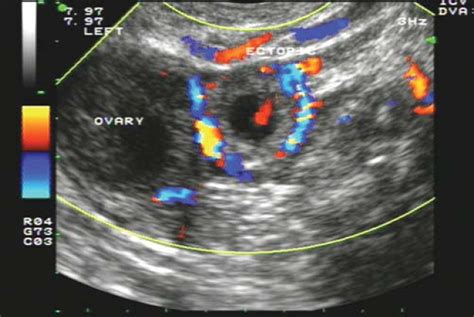

When a physician suspects an ectopic pregnancy, they often perform a transvaginal ultrasound. This procedure uses a specialized wand to provide a high-resolution view of the reproductive organs. By visualizing the uterus, ovaries, and the surrounding areas, radiologists and OB/GYNs look for specific clinical markers.

When doctors look for an ectopic pregnancy by ultrasound, they are essentially looking for an "empty" uterus where there should be a pregnancy sac. The diagnostic process typically involves:

• Locating Adnexal Masses: A mass outside the uterus in the adnexal region (where the fallopian tubes and ovaries are located) often suggests an ectopic implantation.

• Checking for Free Fluid: The presence of free fluid in the pelvic cavity, especially in the pouch of Douglas, can indicate internal bleeding caused by a rupture.